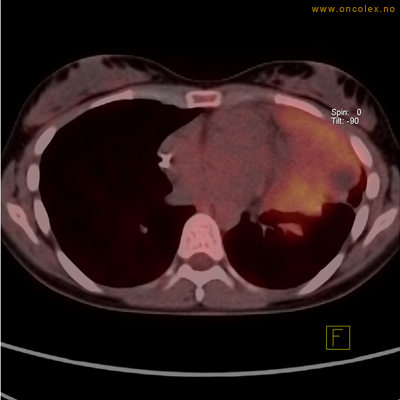

Vev som tar opp mer radioaktivt stoff, synes som hvite områder som lyser opp mer i forhold til annet vev som tar opp mindre sukker.

Moderat opptak av FDG i bløtvevssarkom venstre halvdel av brystkassen. Områder med lavere opptak antas å skyldes dels betennelse som skyldes svulst, dels svulstnekrose.

Kraftig opptak i svulst i lunge.

Lungekreft med spredning til lymfeknute i lungehilus.